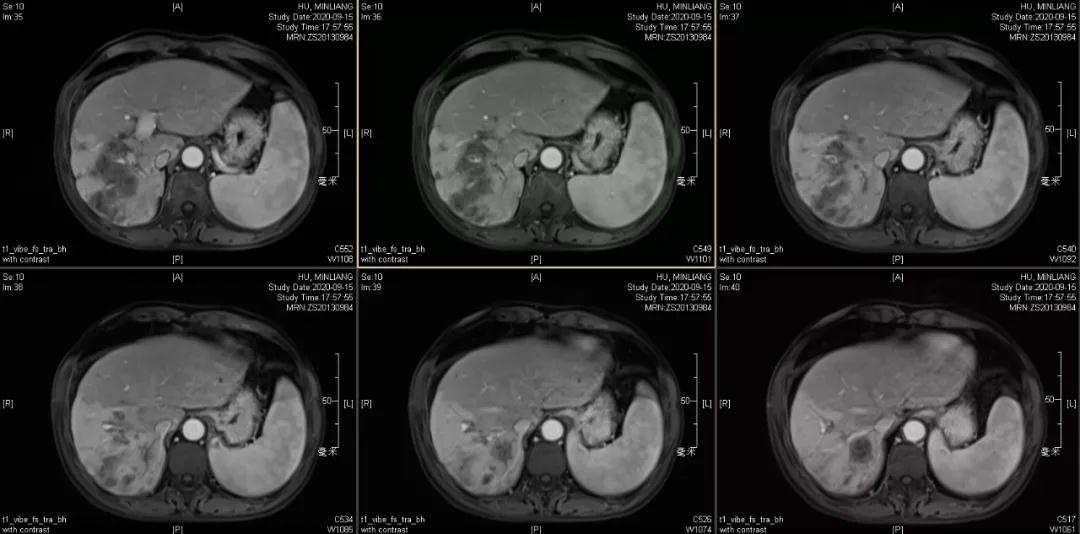

肿瘤学评估(用药后2个月对比6个月):肝内主瘤明显缩小,动脉期强化降低;子灶消失;门脉右支癌栓明显缩小坏死;肺转移灶缩小,大部分消失。

2020-09-15

Δ治疗过程中病灶影像学变化

用药6个月后:肝脏病灶明显缩小,子灶消失,仅有少量动脉期强化;肺转移单个持续缩小稳定,PET CT活性弱;HBV DNA 转阴;可考虑转化切除。